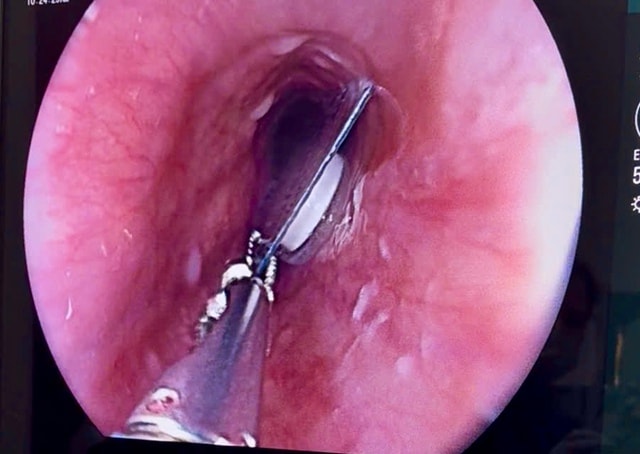

Qua thăm khám, bác sĩ phát hiện khối dị vật nằm 1/3 phía trên thực quản bệnh nhân. Dị vật là viên thuốc còn nguyên trong bao kẽm, kích thước khoảng 1,5 x 1,5 cm. Đây là loại dị vật sắc cạnh, có nguy cơ gây tổn thương niêm mạc thực quản. Các bác sĩ đã tiến hành nội soi gắp dị vật an toàn.